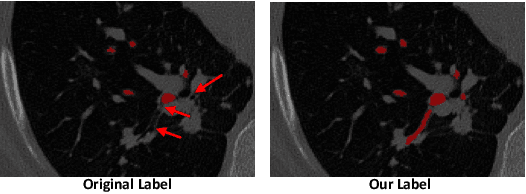

Abstract:Automatic segmentation of the bronchial tree from CT imaging is important, as it provides structural information for disease diagnosis. Despite the merits of previous automatic bronchus segmentation methods, they have paied less attention to the issue we term as \textit{Intensity Confusion}, wherein the intensity values of certain background voxels approach those of the foreground voxels within bronchi. Conversely, the intensity values of some foreground voxels are nearly identical to those of background voxels. This proximity in intensity values introduces significant challenges to neural network methodologies. To address the issue, we introduce a novel Intensity-Distance Guided loss function, which assigns adaptive weights to different image voxels for mining hard samples that cause the intensity confusion. The proposed loss estimates the voxel-level hardness of samples, on the basis of the following intensity and distance priors. We regard a voxel as a hard sample if it is in: (1) the background and has an intensity value close to the bronchus region; (2) the bronchus region and is of higher intensity than most voxels inside the bronchus; (3) the background region and at a short distance from the bronchus. Extensive experiments not only show the superiority of our method compared with the state-of-the-art methods, but also verify that tackling the intensity confusion issue helps to significantly improve bronchus segmentation. Project page: https://github.com/lhaof/ICM.